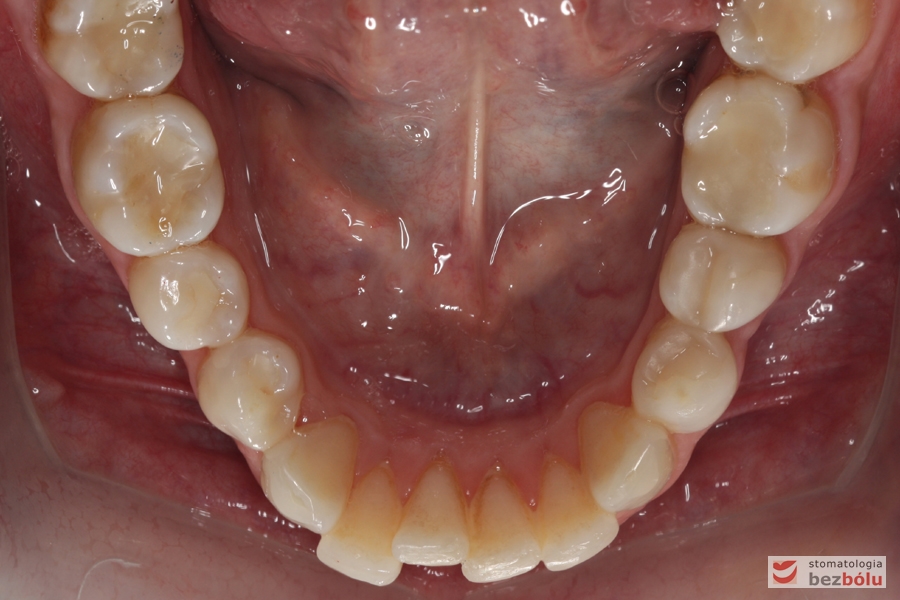

Żuchwa - stłoczenia w rejonie siekaczy, ujemny tork na zębach trzonowych po stronie lewej

Żuchwa – stłoczenia w rejonie siekaczy, ujemny tork na zębach trzonowych po stronie lewej